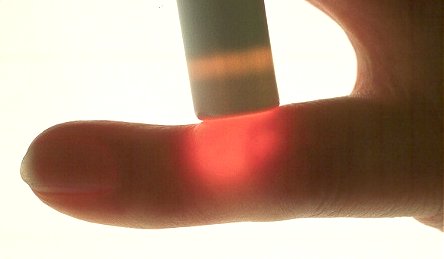

Case 4: similar to case 3.

Flashlight

A picture of the illumination is more obvious with the finger placed on a lit transparency light box.